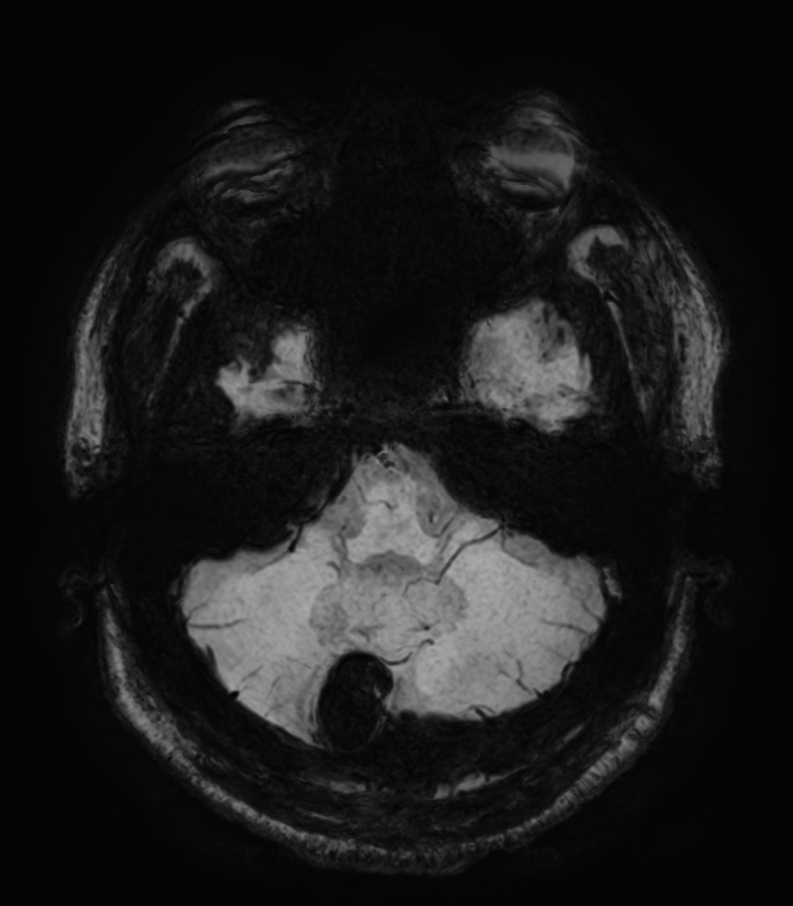

T2w TSE MultiVane XD

-